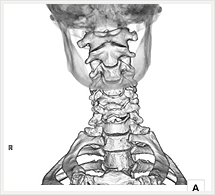

CTでは輪切り像の他にも立体的な画像(3D画像)を作成することもできます。そのためにはより細かくキレイな画像を撮影しなければなりません。当院では64列CTを導入しており、キレイな画像をより細かく撮影することができます。その画像を元に3D画像を作成することによって、より正確な手術のシミュレーションが可能になります。実際に手術をしたときの様子が、手術をする前に画像として見らます。外科系の手術には欠かせない技術となっておりますが、内科系でも血管内手術にも多く利用されております。

当診療放射線技術科では毎日各診療科に対して、その手術に最適な3D画像を提供しております。

以下にその3D画像を一部分紹介します。

脊椎